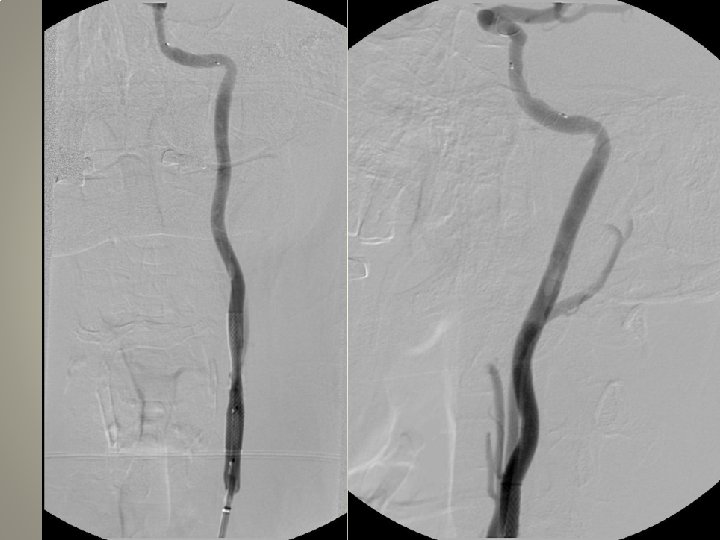

pre-op • • • Karotis stentleme için uygun hazırlık önemli Anti-agregan kullanımı Hassasiyet ölçümü diffüzyon MR: yeni lezyon? İşlem sırasında sedasyon ağrı duyulmasın Kan basıncı monitorizasyonu

Vasküler erişim • Kateterizasyon: uzun re-inforced sheats (terumo, arrow, cook) uzun diagnostik kateter 120/125 cm Hidrofilik (Terumo 0. 035 -38 stiff or roadrunner-Cook) teller Hidrofilik olmayan (amplatz) teller

Uzun kılıf • Standard kılavuz kateterlere oranla artmış stabilite • Geniş lümen • Bükülmeye direnç • Hidorfilik kayganlık, ilerletilebilme

Uzun kılıf • Terumo Destination 6 F, 90 cm, iç lümen • Cook Shuttle, 5 F 90 -110 cm, 0. 074 inch 6 F 80 -110 cm, 0. 087 inch • Arrow…….